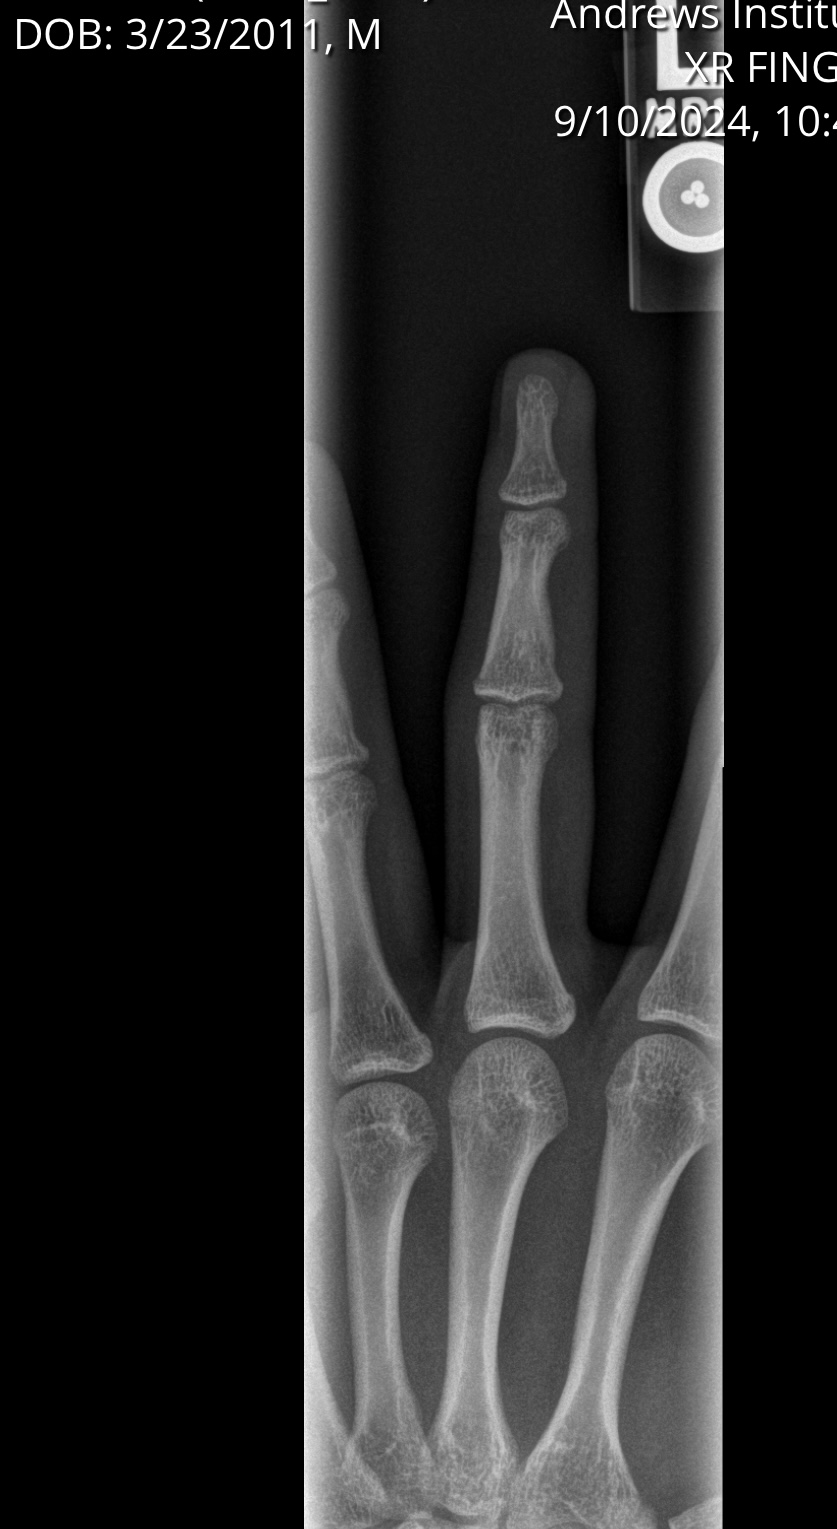

Based off this x ray that I got around a year and a half ago do you guys think I am still growing? I’m 5’11 and I’ve noticed that I haven’t grown in a while so I want to know if I’m done growing. Is 6’3 possible?

The photo seems to have gotten squished. Hopefully this is better

closed. you can ask the doctor who took these xrays. Mine told me my plates were shut without me even asking a few weeks ago